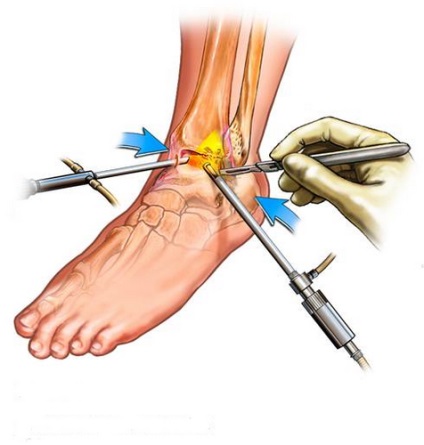

În cazul în care sinovită necesită o intervenție chirurgicală, de exemplu, în caz de deteriorare sau slăbiciune a ligamentelor, hipertrofie sinovială, nu trebuie să nu puncție, și artroscopie, și în timp ce efectuează funcții de diagnosticare și chirurgicale.